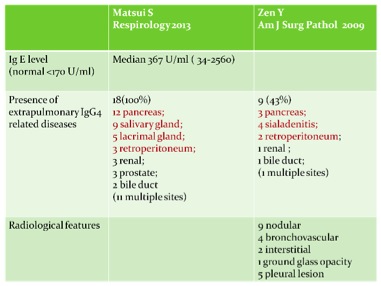

There is still no published consensus about the diagnostic criteria of igG4-related disease. Most studies are using diagnostic criteria by Umehara and colleagues in 2011: 1) clinically showing characteristic diffuse or localized swelling or masses in single or multiple organs, 2) hematological examination shows increased serum IgG4 concentration, 3) histopathologic examination showing a) marked lymphocyte and plasmacytic infiltration and fibrosis, and, b) infiltration of IgG4 + plasma cells: ratio of IgG4+/IgG+ cells more than 40% and more than 10 IgG4+ plasma cells per high power field. Patient can be diagnosed as definite (fulfill all 3 criteria), probable (fulfill the 1st and 3rd criteria), and possible (fulfill the 1st and 2nd criteria) IgG4-related disease (3). According to 2 series from Japan, the incidence of lung involvement of IgG4-related disease can range from 14 to 54% (4,5). There are two relatively large scale case series published by Matsui S in Respirology 2013 and Zen Y in Am J Surg Pathol 2009 to describe the clinical features of patients with IgG4-related lung disease. Both series showed male predominance around 80%. There were 12% and 43% of patients in respective series having allergic history like rhinosinusitis and asthma. Only 28% and 47% of patient in respective series having pulmonary symptoms and mostly complained cough. The radiological features of lung manifestation were described in Zen study, which can be nodular, bronchovascular interstitial, ground-glass opacity or pleural lesion. (table 2,3) The possible radiological findings of IgG4-related lung disease were also described in review article by Ryu in Eur Respi J 2012 (table 4) (6).